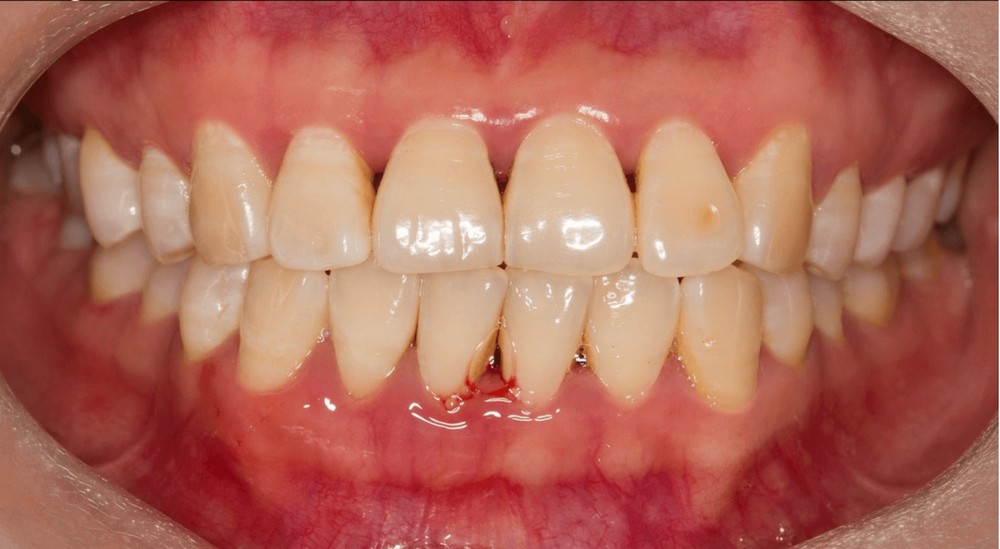

Ở giai đoạn này, tình trạng viêm nướu răng thường không gây ra cảm giác đau đớn. Triệu chứng của nó bao gồm lợi sưng đỏ, phồng lên và khi đánh răng có thể gây ra chảy máu do bị tác động mạnh. Viêm nướu cục bộ chưa ảnh hưởng nhiều đến chân răng và các thành phần xung quanh răng.

Trong giai đoạn này, lợi sẽ sưng đỏ, chảy máu nhiều hơn, gây ra cảm giác đau nhức dữ dội và có thể kèm theo các hiện tượng sưng má. Đặc biệt, tình trạng này có thể làm hơi thở có mùi hôi khó chịu. Nếu không được điều trị kịp thời, lợi sẽ tụt xuống, làm cho chân răng bị lộ ra và dần dần sẽ bị rụng răng.